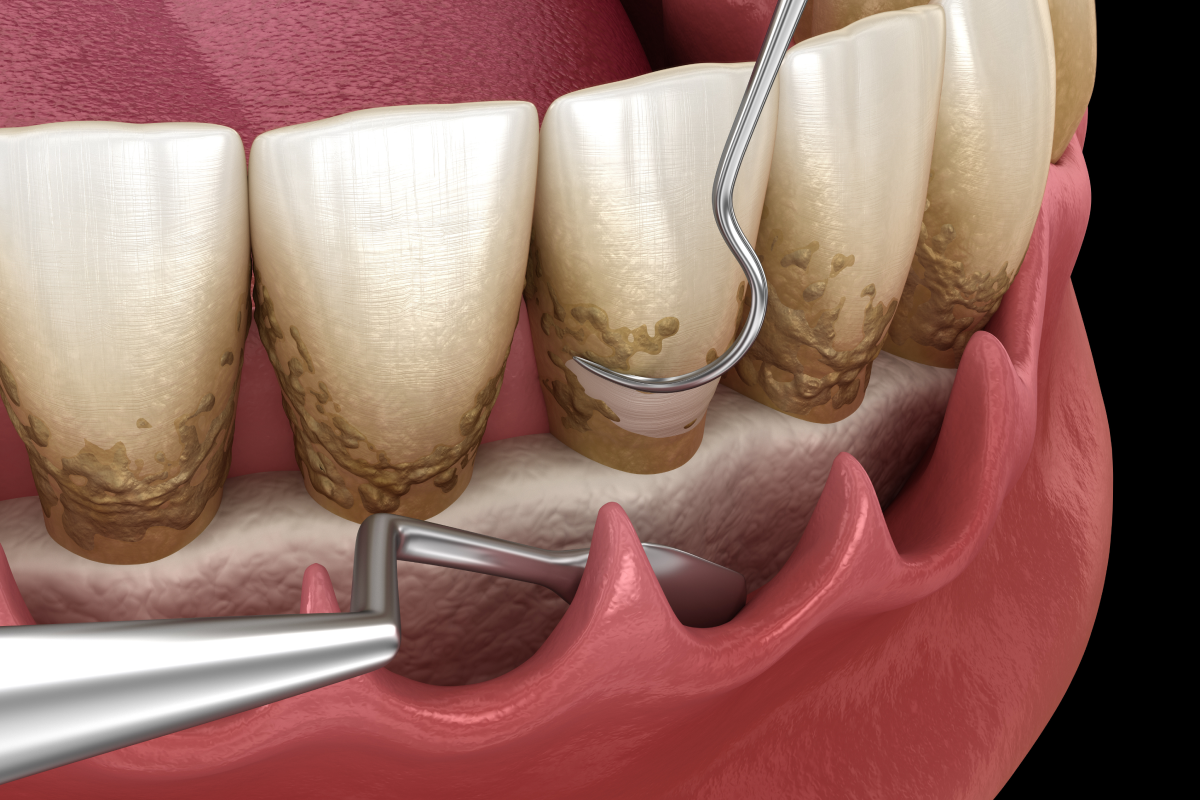

Soins médicaux des gencives

Les soins des gencives visent à prévenir, détecter et traiter les inflammations ou infections qui peuvent fragiliser les tissus de soutien des dents.

Soins chirurgicaux des gencives

Nous réalisons une chirurgie des gencives lorsque les traitements non chirurgicaux ne suffisent plus.